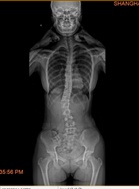

以往案例

我们相信通过专业训练,为您解决脊柱侧凸的困扰,重拾自信,拥有健康挺拔的身姿。

脊柱侧凸又称为脊柱侧弯畸形,是一种复杂的脊柱三维畸形,主要表现为脊柱一个或多个节段向侧方发生弯曲或伴有椎体旋转。侧凸后脊柱常呈现“C”形或者“S”形。